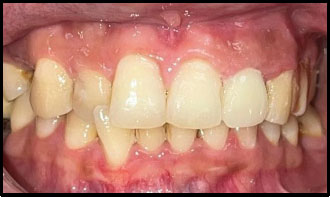

Peeso reamers (sizes 1 and 2) were used for post-space preparation, making sure that 3–4 mm of gutta-percha was retained at the apex. Next, a dual-cure resin cement was used to lute a prefabricated fiber-reinforced post into the canal (Fig. 3). Once the fiber post was in position (Fig. 4). Composite resin was then used to build up the core (Fig. 5). Occlusal view of the core build-up is shown in Fig. (6). Finally, a highly translucent all-ceramic crown was placed, restoring the tooth’s function and aesthetics in alignment with the surrounding dentition in occlusion (Fig. 7) and Occlusal view (Fig. 8).

Post operative.

Post operative - occlusal view.